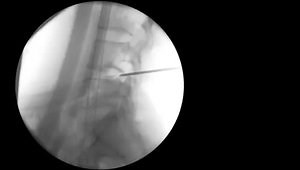

Transforaminal Endoscopic Lumbar Discectomy

Step by Step Technique Transforaminal Endoscopic Lumbar Discectomy Operation under Analgo-Sedation in Daysurgery

Endoscopic Approach to Transforaminal Discectomy

Transforaminal Endoscopic Discectomy: Tips and Tricks

Right L4-5 Laser Endoscopic Transforaminal Discectomy

Transforaminal endoscopic discectomy L4-5

Transforaminal Endoscopic Discectomy